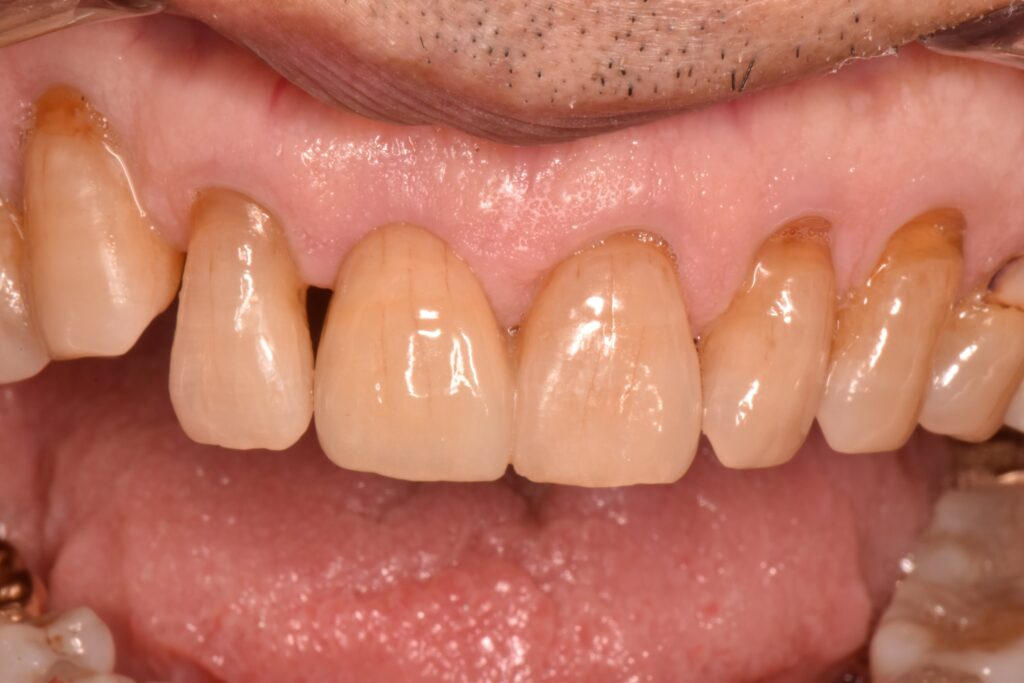

歯ぐきが綺麗に治癒するとこのように歯ぐきが凹んだ形となります。

片方の裏側だけに支えを持たせて、接着を行いました。支えとなっている部位はほとんど削らずに治療をしています。

抜歯直後から治療を行ったことで可能な限り審美的に治療を行うことができました。

接着ブリッジによる治療は、脱離するリスクは報告されていますが、長期に生存することが論文的に証明されています。歯をほとんど削っていないことは、とても大きなメリットだと思います😊